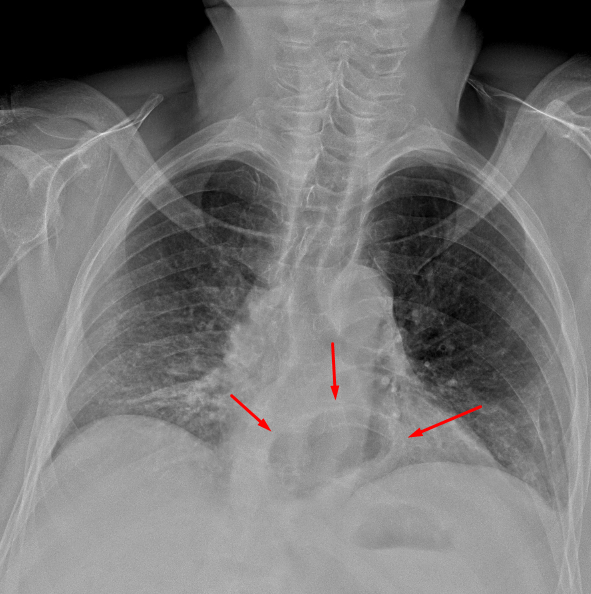

Age: 66

Sex: Male

Indication: Chest pain

Sample ReportStreaky bibasilar opacities likely represent atelectasis. Otherwise, no evidence of acute cardiopulmonary disease.

Moderate sized hiatal hernia.